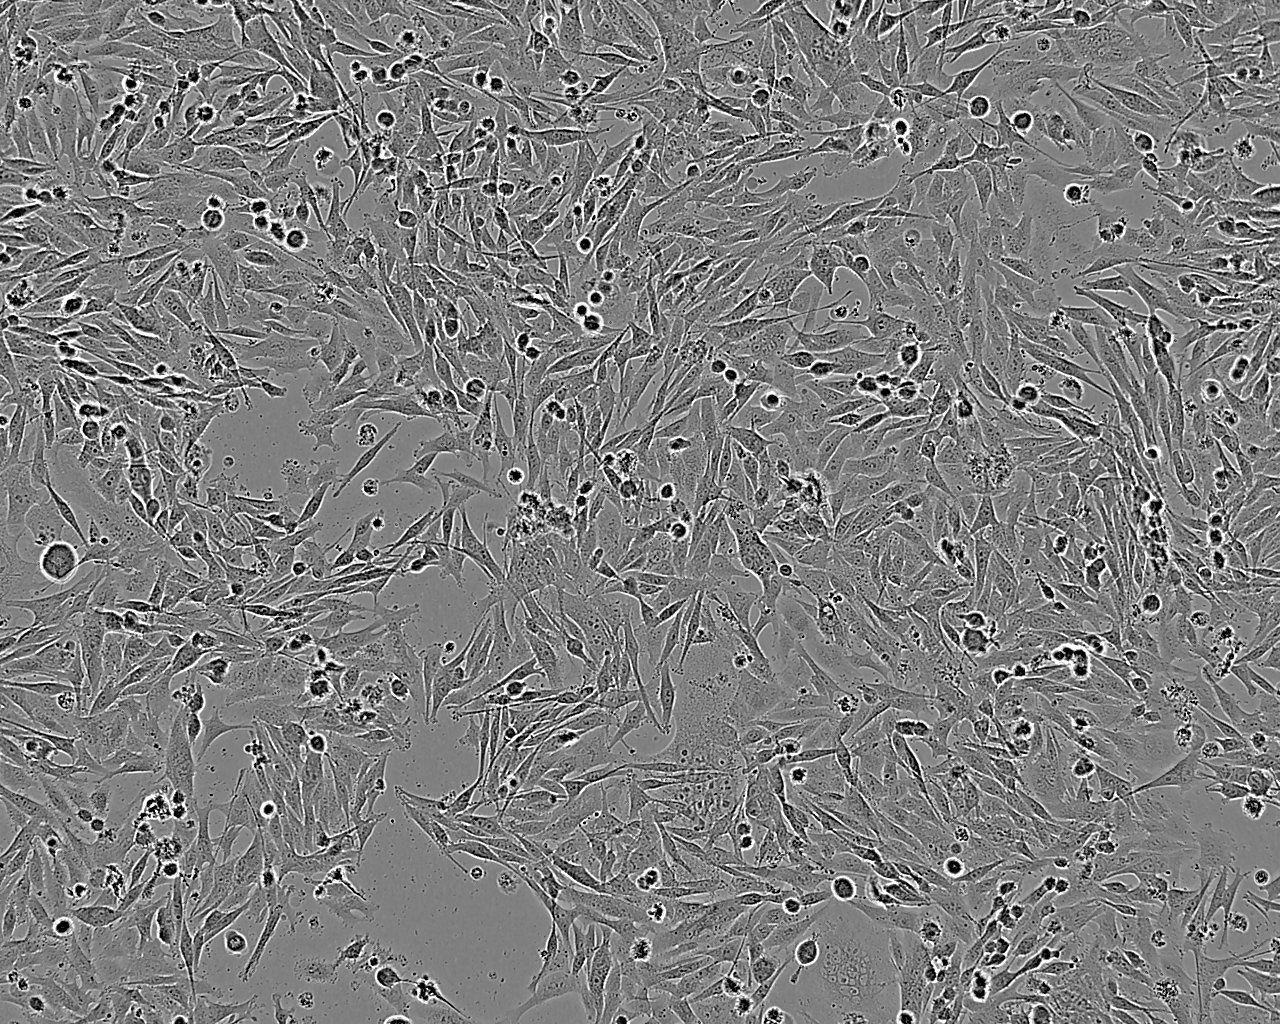

Images

Derived from a pelvic wall metastasis of a 69 year old female with colon carcinoma.

Cell Type

Growth Mode